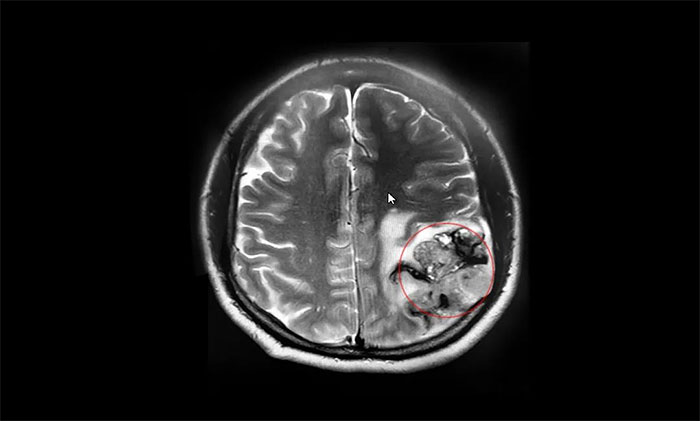

▲ MRI显示肿瘤最大直径超7厘米大小

因着这一线生机,张先生再次带着妻子来到上海,转入上海蓝十字脑科医院。入院检查时,头颅MRI平扫+增强提示:左侧额顶叶占位性病变,最大径约4.2×7.4×4.3cm,如鹅蛋般大小。